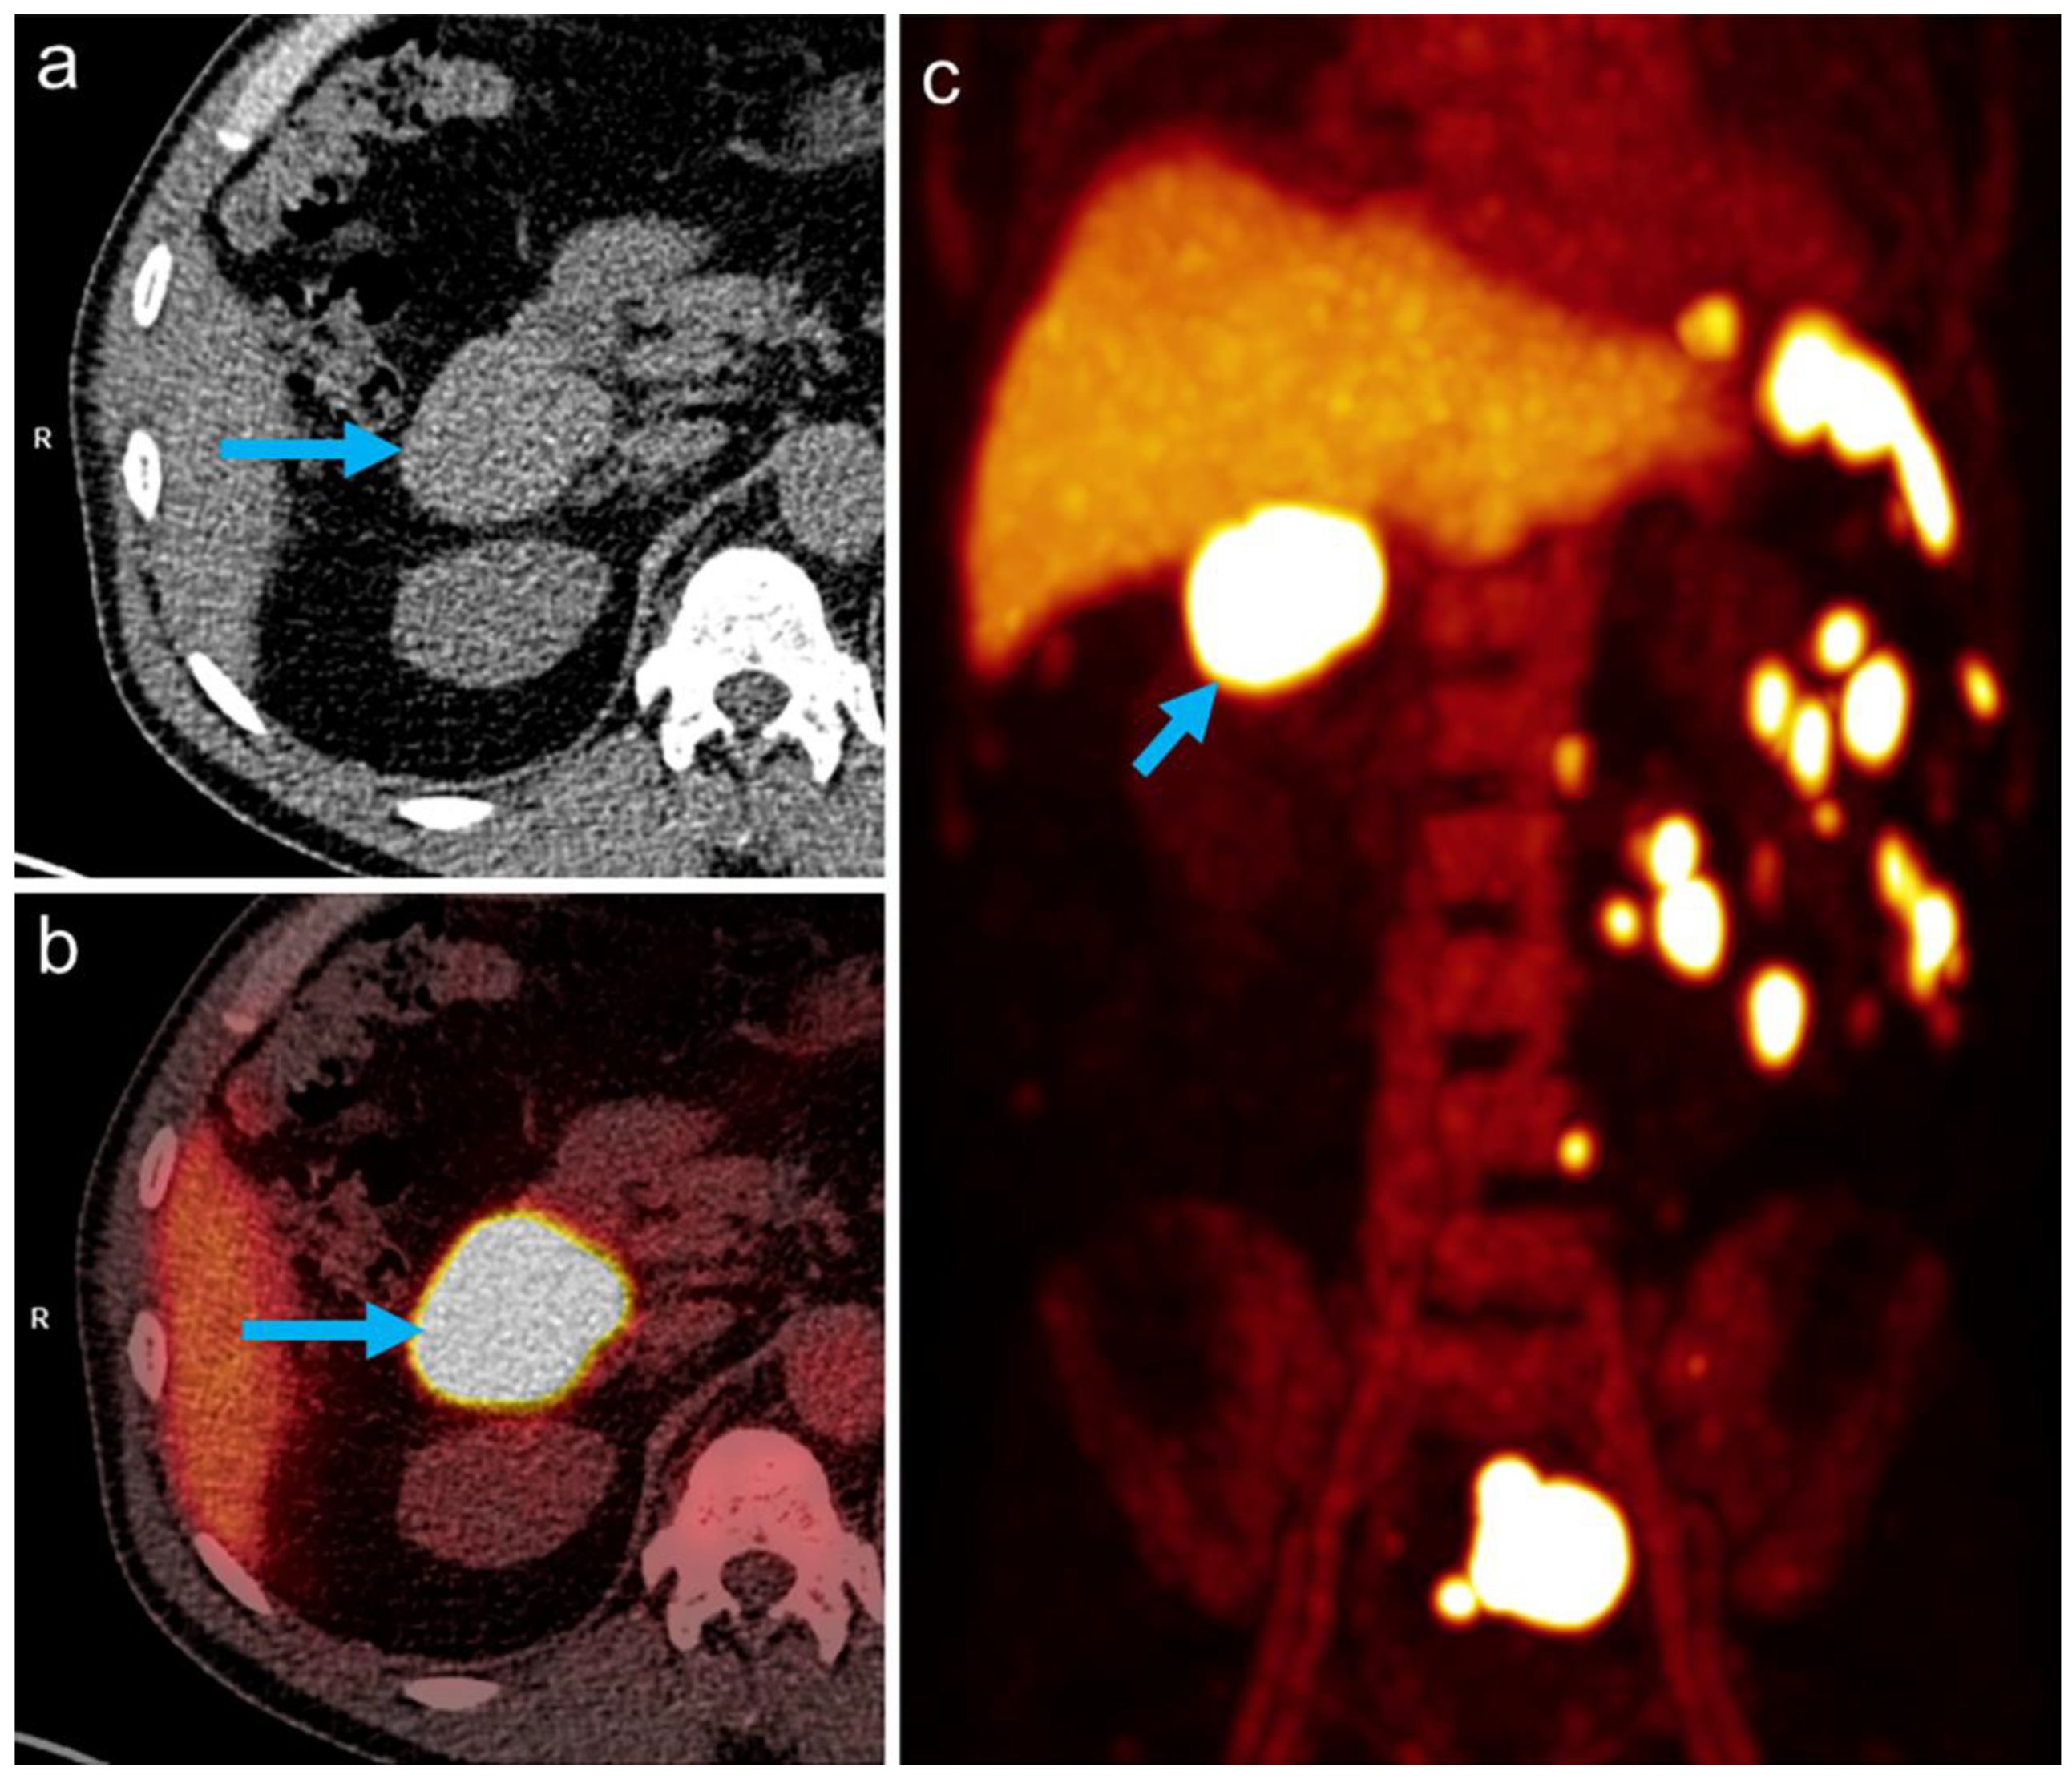

Initially, a malignant disease, particularly a lymphoma, was suspected, and magnetic resonance imaging (MRI) of the abdomen was performed for further evaluation. This confirmed the partially lobulated, well-defined lesions (Figure 1). In view of the previous surgery and the missing spleen, the differential diagnosis of multilocular ectopic splenic tissue (splenosis) was considered.

Figure 1. MR imaging showed well-defined masses (arrow: index lesion in the upper abdomen), moderately hyperintense on T2-weighted spectral presaturation with inversion recovery (SPIR) images (a) and with nearly homogeneous contrast enhancement on T1-weighted multiecho 2-point Dixon (mDIXON) sequences (b).